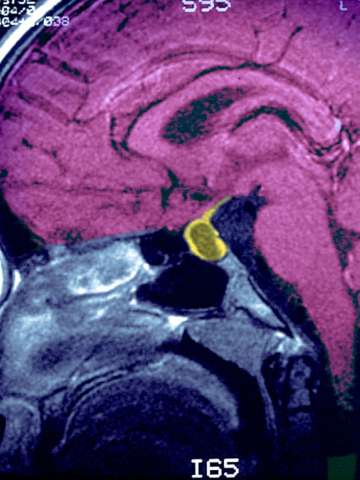

Pituitary Tumor Scan